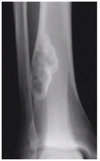

• Descreva a lesão:

A

• Osso esqueleticamente maduro

• Localizada no fêmur distal, predominantemente metafisária, acometendo medula e cortical

• Lesão única, de grande dimensão

• Lítica

• Sem padrões de conteúdo em específico

• Margens mal definidas

• Rompe a cortical medial, lateral e posterior

• Possui extensão para partes moles

• Sem reação periosteal visível